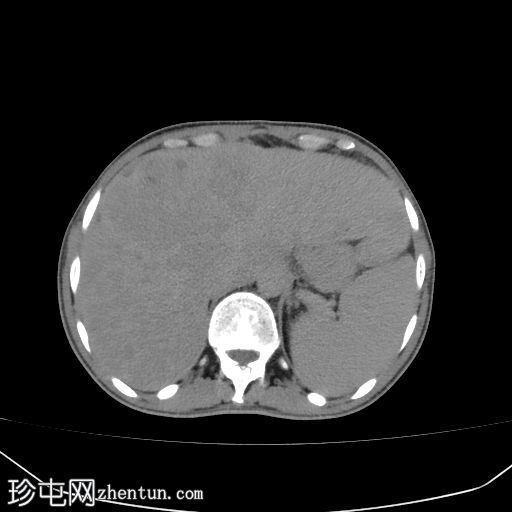

腹部(肝脏)CT

轴位

轴位增强扫描

门静脉期

肝硬化征象包括表面和实质结节、实质异质性、右后肝切迹征和容积重分布。

门静脉可见肿瘤血栓,表现为血栓强化。

肝脏可见无数细小病灶,动脉期呈非环状强化,门静脉期呈消退,提示弥漫性肝细胞癌。

其他发现包括腹水和左侧肾上腺可疑增厚。